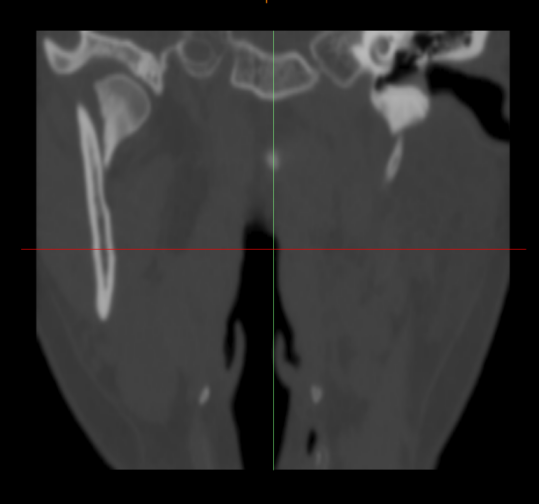

术前照片

老百姓口中的“下巴”,指的是面部下颌骨区域,医学专业上特指下颌骨前部中份的颏部。颏部因位置突出靠前,受伤瞬间人体反应等因素,容易造成直接损伤,形成软组织裂伤及下颌骨中间部分骨折。然而,由于下颌骨呈马蹄形结构,两侧向上借助升支形成的髁突与颅底结构形成颞下颌关节,如果颏部的直接外力过大,力量沿升支传导向上,就可能造成下颌骨髁突骨折。

髁突骨折较一般下颌骨骨折相对复杂。首先,髁突参与形成颞下颌关节,该关节是人体最灵活、功能最复杂的关节之一,一旦遭受损伤,可能出现咬合紊乱、张口受限、关节强直、关节炎等症状;由于髁突为生长发育中心,未成年人还可能影响颌面部的发育。其次,髁突骨折分类及相应治疗原则多样,根据骨折的部位可简易分成髁头、髁颈、髁基骨折,每种分类又根据移位等情况可分为不同亚型,不同分类亚型需正确选择手术适应症,才能达到最佳治疗效果。第三,髁突手术涉及支配面部表情肌的运动神经—面神经,分泌唾液的大腺体—腮腺等重要解剖结构,需熟练掌握手术技巧,以免出现面瘫等影响患者美观的并发症。